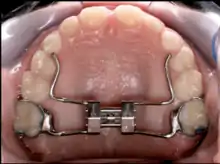

A palatal expander

A palatal expander is a device in the field of orthodontics which is used to widen the upper jaw (maxilla)[1] so that the bottom and upper teeth will fit together better.[2][3] This is a common orthodontic procedure. Although the use of an expander is most common in children and adolescents 8–18 years of age, it can also be used in adults, although expansion is slightly more uncomfortable and takes longer. A patient who would rather not wait several months for the end result by a palatal expander may be able to opt for a surgical separation of the maxilla. Use of a palatal expander is most often followed by braces to then straighten the teeth.